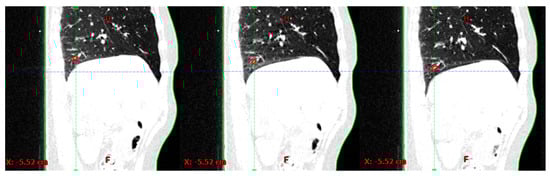

Using the Eclipse treatment planning system (TPS) (Varian Medical Systems, Palo Alto, CA, USA), a segment of a blood vessel in the lower right lung lobe, i.e., the target structure (TS), and the patient’s skin (skin structure) was generated on the first of the 10 4DCT phases and propagated to the other phases; see Figure 1.

Figure 1.

An example of a tracking structure (TS) (red) and skin (green) in three out of ten 4DCT phases.